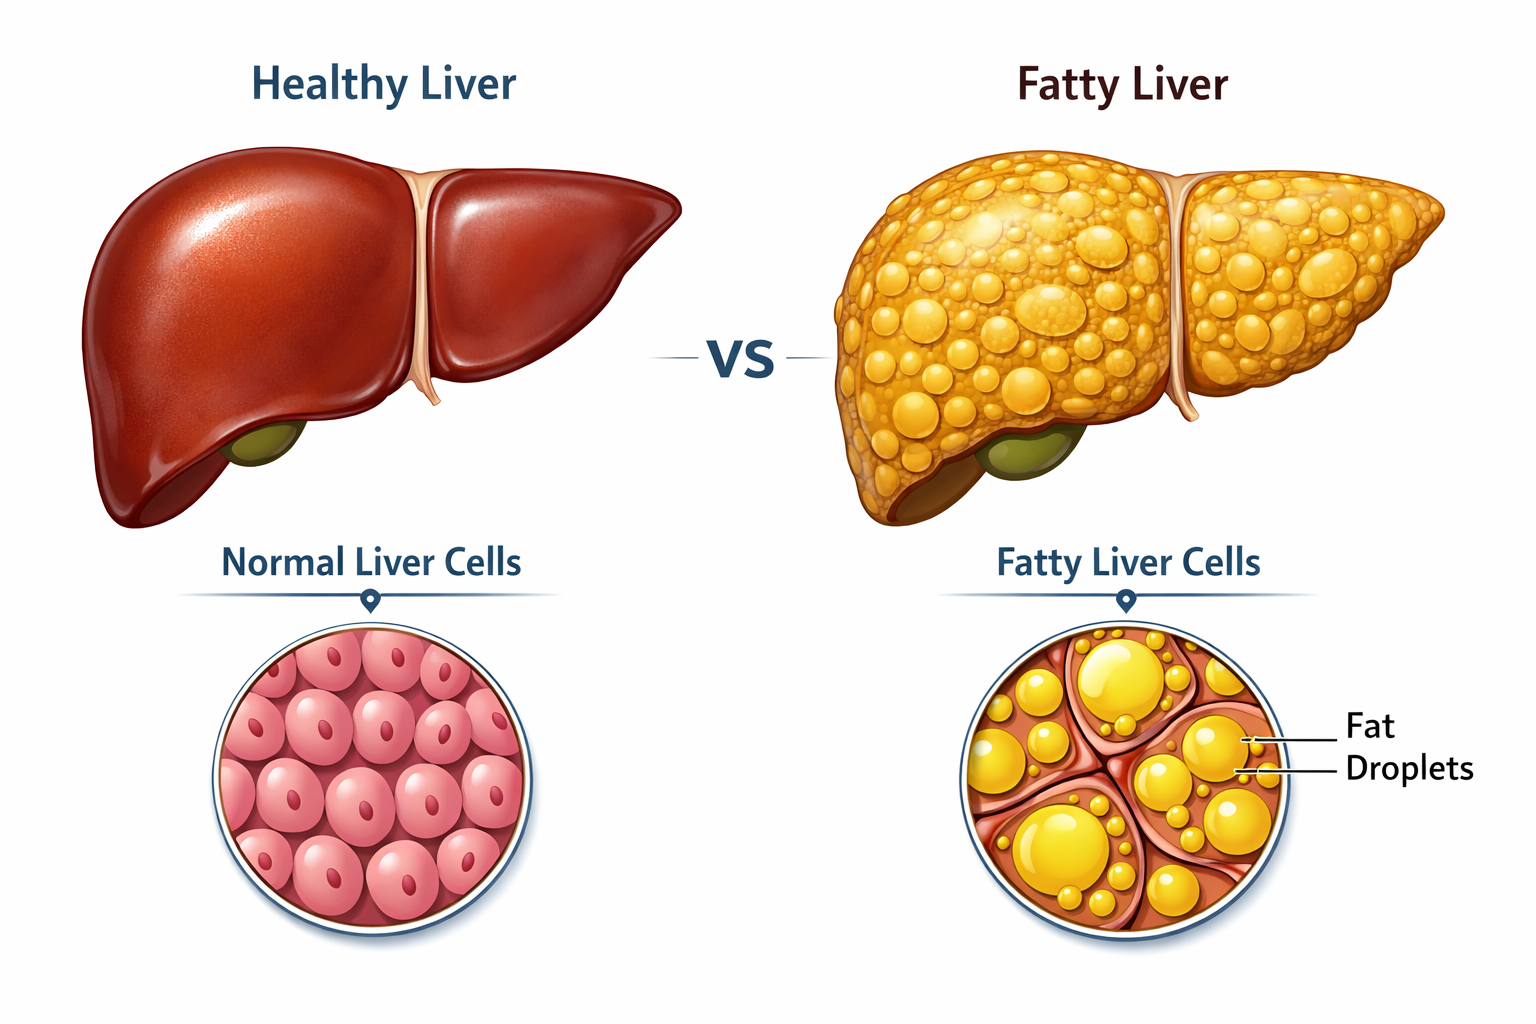

Looking for Hepatitis C treatment in Hyderabad? Dr Rahul Dubbaka offers advanced antiviral therapy with 95%+ cure rates at People’s Hospital, Pragathi Nagar. Book your consultation today at +91 9100921514. Hepatitis C is a viral infection that primarily affects the liver and can silently damage it over time. If left untreated, it may lead to serious complications such as cirrhosis, liver failure, and even liver cancer. The good news is that with modern medical advancements, Hepatitis C is now highly curable with effective antiviral medications.

Hepatitis C is caused by the Hepatitis C virus (HCV). It spreads mainly through contact with infected blood. Many people with Hepatitis C do not experience noticeable symptoms initially, which is why the infection often remains undiagnosed for years.

Over time, chronic Hepatitis C can cause progressive liver inflammation, leading to fibrosis (scarring), cirrhosis, and increased risk of liver cancer.

Complications of Untreated Hepatitis C

If not treated, Hepatitis C may lead to:

Liver cirrhosis

Liver failure

Portal hypertension

Ascites

Liver cancer (Hepatocellular carcinoma)

Early treatment prevents these complications and improves life expectancy.